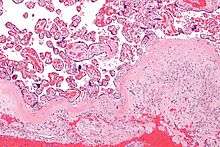

Micrograph of decidua in a lymph node. H&E stain.

The decidua has a histologically-distinct appearance, displaying large polygonal decidual cells in the stroma. These are enlarged endometrial stromal cells, which resemble epithelium (and are referred to as "epithelioid").

The region of fibrinoid degeneration where trophoblasts meet decidua is called Nitabuch's layer. This layer is absent in placenta accreta.[1]